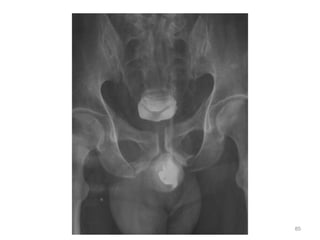

Identify source of bleeding and control

Pelvic fracture

Pelvic fracture Dx?

Source of bleeding ?

Mx?

Splenic injury Mx?

Liver laceration Mx ?

41

Adjuncts to Primary Survey

• Radiology

– C-spine, CXR, Pelvis

– FAST